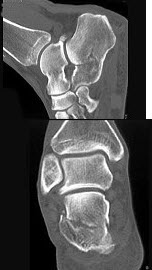

47、单项选择题

男,36岁,从高处摔下,足部受伤,结合图像,最可能的诊断是()

A.距骨骨折

B.跟骨骨折

C.骰骨骨折

D.舟状骨骨折

E.楔骨骨折